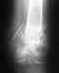

Перелом таранной кости.

Здравствуйте врачи-травматологи.Помогите мне ходить нормально.Я в июне 20-ого совершил ДТП,и у меня сломалось таранная кость.Оперировали но ходить нормально еще не могу.Сегодня прошел КТ.Врачи говорят опять на операцию надо.Но я не доверяю им.Потому что они говорят ходить по прежнему я не смогу.Если есть опытные врачи-травматологи прошу вас откликнитесь и подскажите ваш адрес.Заранее спасибо.